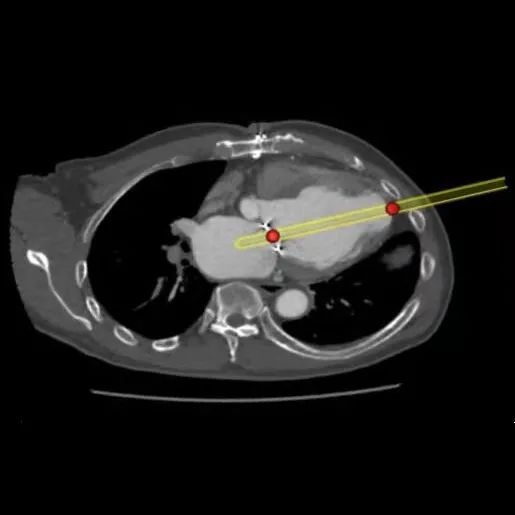

患者二尖瓣位可见人工成形瓣环(30# Physio),成形环平均内径23.6mm,有效开口面积435.7mm²,模拟Prizvalve®瓣膜系统26mm瓣膜植入,显示左心室流出道剩余面积511.6mm²。

术前食道超声和造影显示:二尖瓣成形术后表现,中重度二尖瓣反流,二维描计估测瓣口面积约4.1cm²。